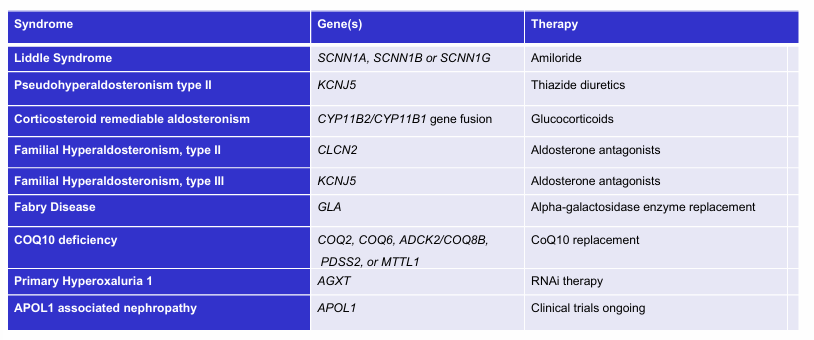

monogenic kidney disease with specific therapies- syndrome, gene(s), therapy